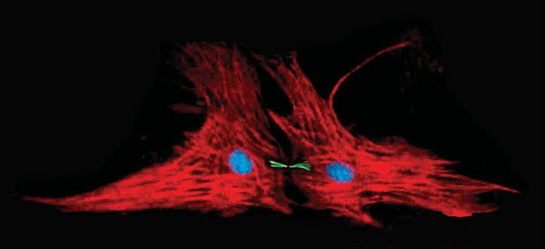

Studiuesi i cili ka marrë përsipër këtë studim ështe Alexander B. Niculescu III, i cili deklaron që molekula ARN që gjendet në gjak është çelësi i zbulimit. Ai shprehet se si rezultat i studimit të bërë tregohet se personat që kanë prezencë më të madhe të kësaj molekule në gjak, kanë prirje për vetëvrasje.

Gjatë këtij studimi janë mbajtur në vëzhgim disa persona, të cilët kishin tentuar më parë për t’i dhënë fund jetës së tyre dhe rezultoi që kishin çrregullime në sistemin nervor dhe disa persona normal. Tek personat me çrregullime në sistemin nervor vihej re rritje e ARN-së sa herë tentonin të kryenin vetëvrasjen. Sipas studimit rezultuan mbi 1 milion persona qe vrasin veten.